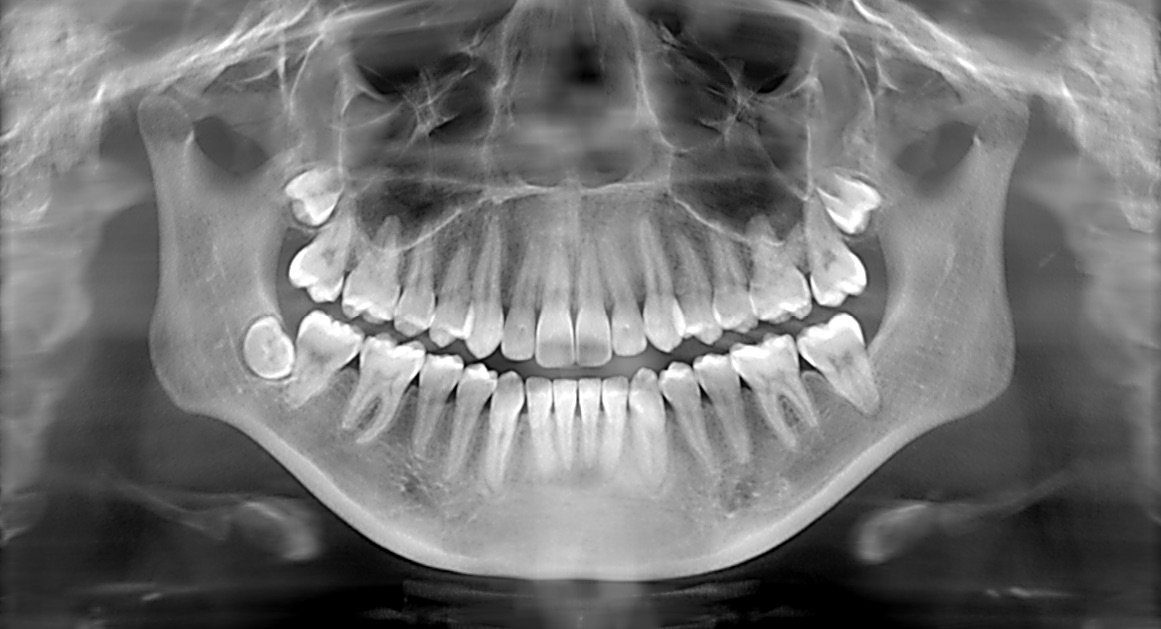

Enter precision diagnostics with dental X-rays, a revolutionary solution designed to tackle such issues head-on. These advanced X-rays offer unparalleled accuracy, allowing dentists to identify hidden dental problems that might not be visible during a regular check-up. For Riya, this meant getting to the heart of her dental issue swiftly and effectively, saving her time, pain, and the potential for more serious dental complications in the future.

The turning point in Riya's story came during a routine visit to City Smiles Dental Clinic. Dr. Ananya Kapoor, a renowned dentist known for her patient-centric approach, recommended precision diagnostics with dental X-rays. Dr. Ananya explained, "These X-rays are like a GPS for your mouth. They guide us to pinpoint issues with remarkable accuracy, ensuring we address the problem directly without unnecessary treatments."

Riya, intrigued by the promise of a definitive diagnosis, agreed to the procedure. The results were nothing short of transformative. The X-rays revealed a hidden cavity beneath an old filling, something that would have remained undetected through traditional examination methods. With this newfound clarity, Dr. Ananya promptly devised a treatment plan tailored to Riya's specific needs, addressing the cavity and alleviating her discomfort once and for all.